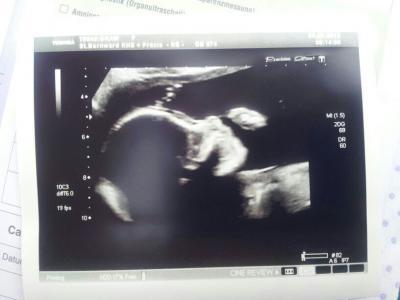

Hallo ihr lieben, wieso ich es nur sporadisch schaffe zu schreiben ist mir echt schleierhaft. Hatte diese woche feindiagnostik und trotz meines Bluthochdrucks ist alles bestens, stolze 400g, 25cm und definitiv ein Mädchen Nächster Termin am 9.7. Mit OGTT Bei einem Namen sind wir uns auch schon recht sicher, die keine Maus wird wohl Charlotta heißen. Verdammt aktiv ist sie und tritt sehr viel und ordentlich. Anbei noch ein Babybild von donnerstag und das letzte Bauchbild

Bild zu Feindiagnostik + Outing + Name + Babybauchbild + Entschuldigung - Forum für November - Mamis